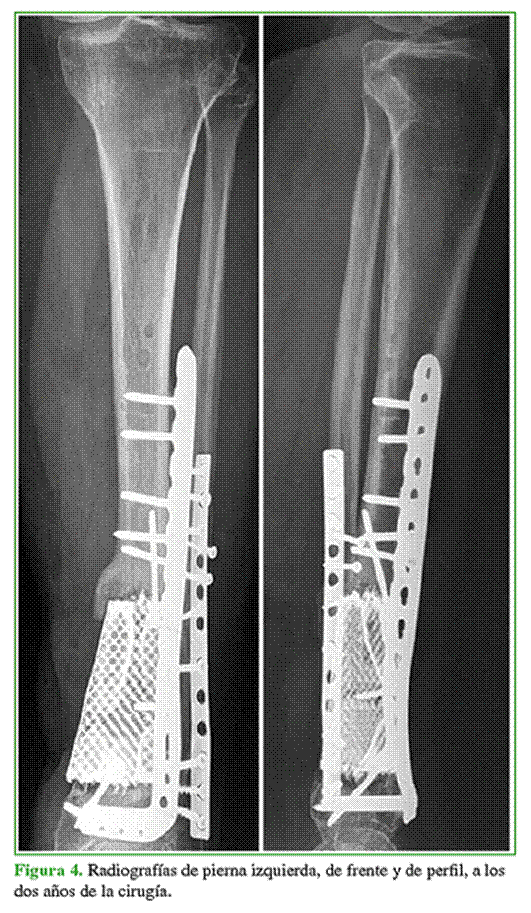

Desarrollo del implante

Se desarrollaron guías de corte para regularizar los bordes fracturarios y determinar la longitud de la resección, y un implante en titanio trabecular diseñado para la colocación de tornillos interfragmentarios en compresión tanto a nivel proximal como distal. En la interfaz implante-hueso, también se emplearon spikes para interdigitar la superficie ósea-implante a fin de aumentar la superficie de contacto y la estabilidad. Se optó por el diseño de un orificio oval pensado para alojar tornillos de una placa LCP regional de tibia anterolateral (Depuy, Synthes) (Figura 3) colocada a modo de neutralización para evitar la pérdida de reducción y el desplazamiento eventual del implante (Figura 4).